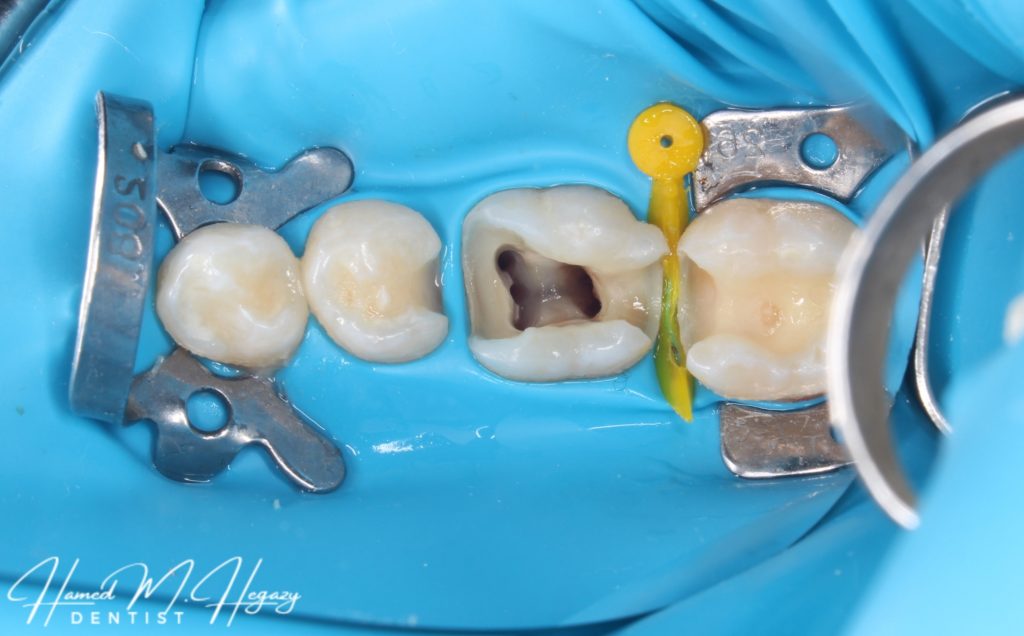

Access cavity

5 canals in lower 6

Middle Mesial canal